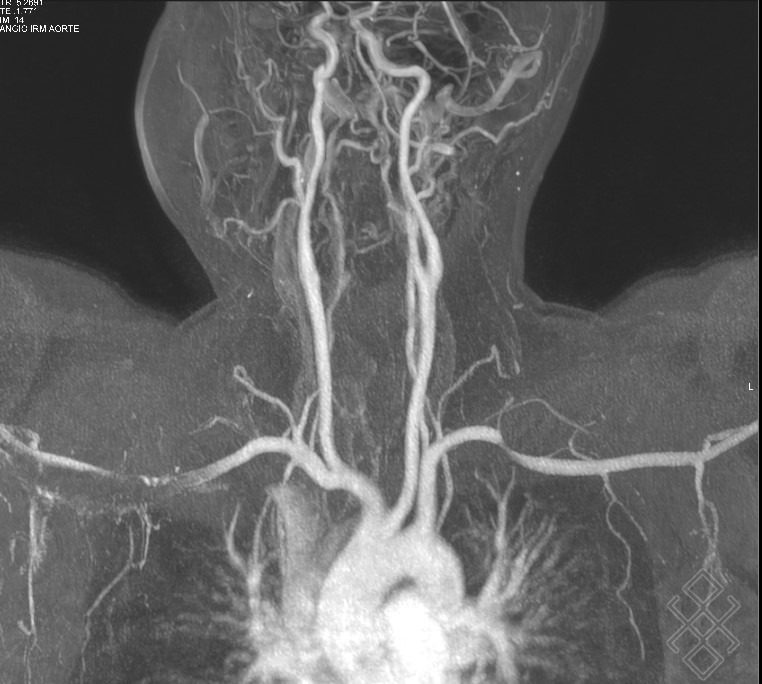

angioirm cérébrale en 3d temps de vol sténoses des artères… Download Scientific Diagram

angioirm cérébrale en 3d temps de